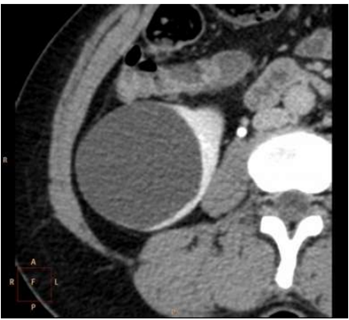

Sobre as imagens a seguir: assinale a alternativa

correspondente à classificação de Bosniak para cada

imagem.

I.

II.

III.

IV.